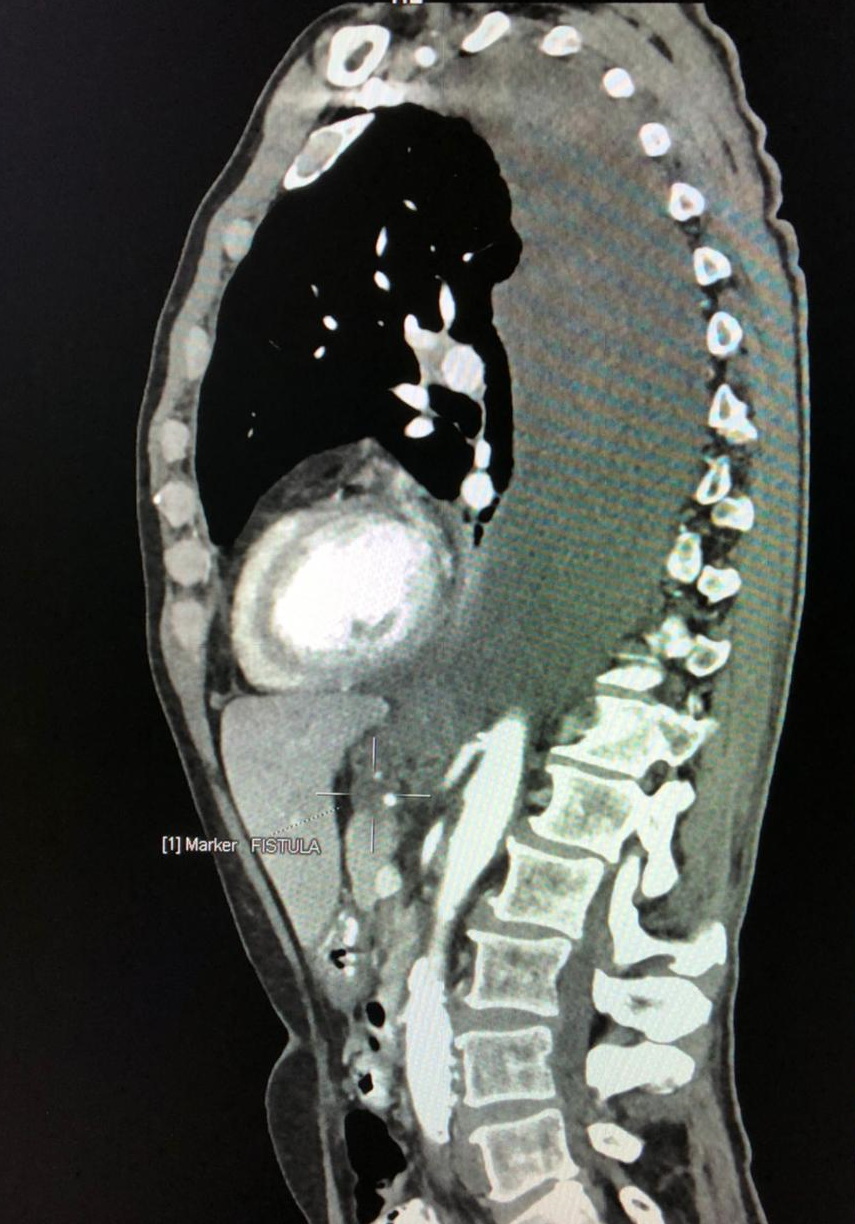

При рентгенографии грудной клетки и ультразвуковом исследовании плевральных полостей в вертикальном положении (06.07.2021 г.) выявлен двухсторонний гидроторакс: справа - до уровня VII-го межреберья, от паравертебральной до задней аксиллярной линии осумкованная жидкость, размерами 13,5х4,9х6,1 см, объемом до 400 мл.; слева - до уровня VI-го межреберья, от лопаточной до средней подмышечной линии, уходя в передние отделы плевральной полости отграниченное жидкостное скопление размерами 15,2х6,1х6,5 см, объемом 600 мл. Жидкостное содержимое однородное, анэхогенное. Сразу же, под ультразвуковым контролем, выполнена пункция и дренирование обеих плевральных полостей, удалено 800 мл транссудата светло-коричневого цвета. При биохимическом исследовании выявлен запредельный уровень амилазы в жидкости - 30 тысяч Ед/л, учитывая данный факт, заподозрен свищ между ПЖ и обеими плевральными полостями. При мультиспиральной компьютерной томографии (МСКТ) органов брюшной полости, грудной клетки с контрастированием и магнитно-резонансной холангиопанкреатографии (МРХПГ) от 07.07.2021 г. диагностирован хронический панкреатит с псевдокистами (до 3 см) в теле ПЖ, а также внутренний билатеральный панкреатикоплевральный свищ, двусторонний ферментативный плеврит (рис. 1).

Рис. 1. Компьютерная томография грудной клетки и органов брюшной полости с контрастированием. Билатеральный панкреатикоплевральный свищ, ферментативный плеврит.

Fig. 1. Computed tomography of the chest and abdominal organs with contrast. Bilateral pancreatic pleural fistula, enzymatic pleurisy.